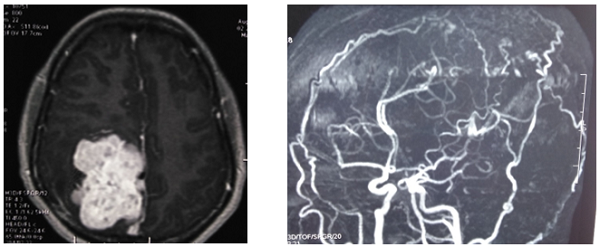

Sau khi tiến hành các bước chẩn đoán và xét nghiệm thường qui, bệnh nhân N được các bác sĩ chuyên khoa Ngoại thần kinh chẩn đoán u màng não khổng lồ bán cầu phải với kích thước  8 x 7 x 5,5 cm3, có nhiều nhánh mạch máu nuôi và xâm lấn xương sọ, nhu mô não, gây phù não và đẩy lệch đường giữa, chèn ép vùng não vận động và cảm giác.

Hình 1: Hình ảnh khối u khổng lồ và mạch máu nuôi u trên phim cộng hưởng từ sọ não